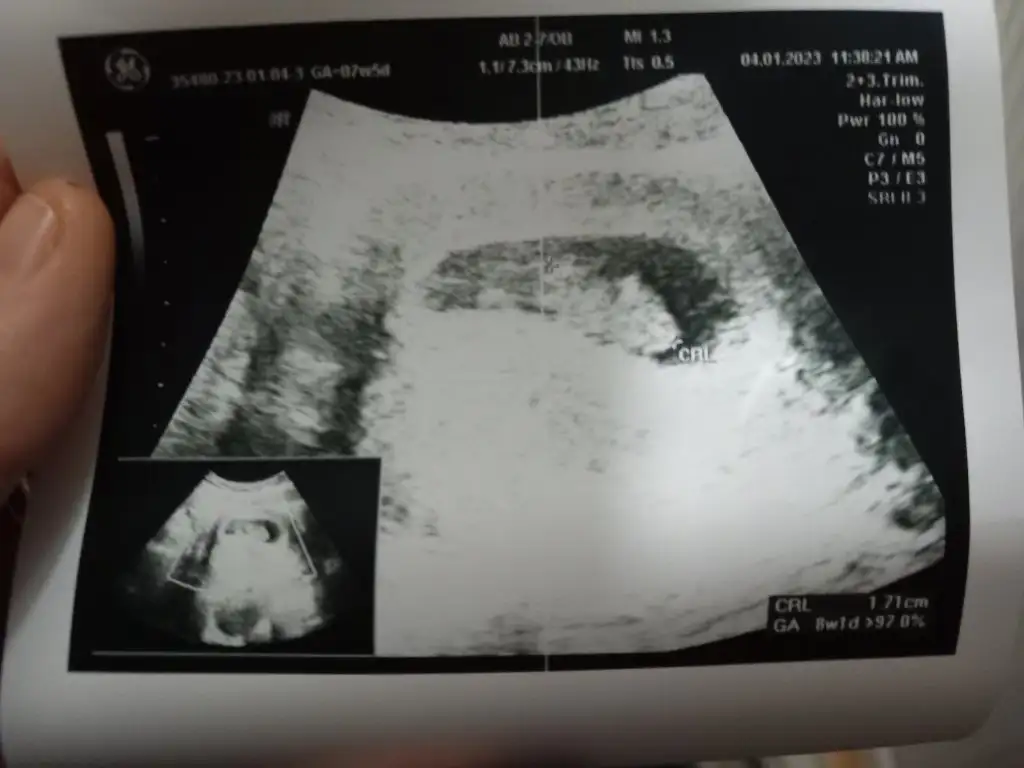

Ben nubdan bakmıyorum canım ama 6-9 haftalık görüntüsü varsa yorumlarım :)

6-9 haftalık fotosunu atarsanız yaparım burda bebişiniz çok büyük böyle bilemiyorum maalesef burda 7 hafta 5 günlük

Maalesef anlayamadım hiç kese olan fotosun yok mu uzaktan bebek daha ufakken

Heh işte böyle fotolar lazım banaEki Görüntüle 3202507 Ya da bu var

Her türlüsü mevcut fotoların da işte ben de ah bi anlasamHeh işte böyle fotolar lazım banaKız gibi geldi canım bana karından ultrasonsa eğer